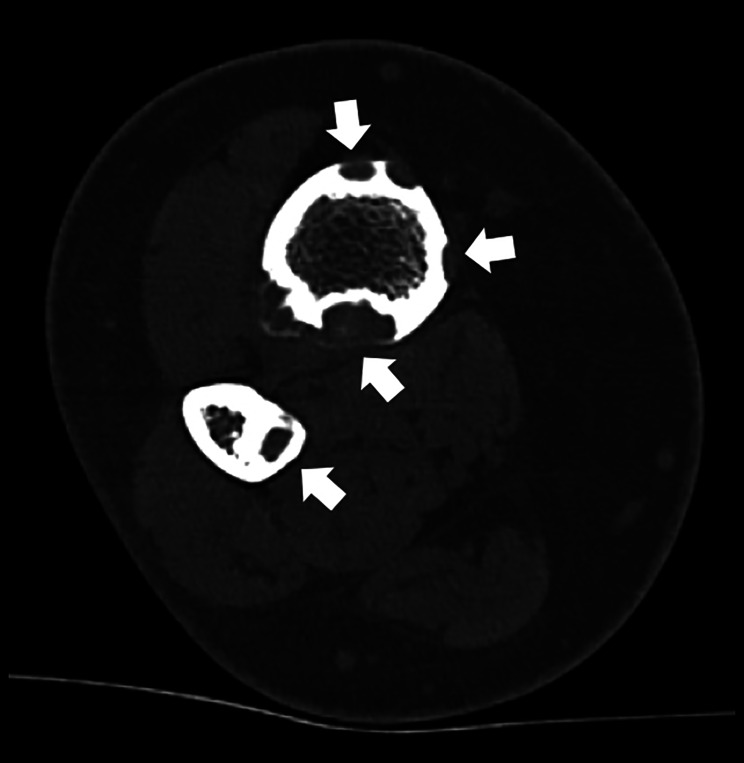

教学点:骨纤维结构不良(OFD)是一种罕见的良性纤维骨性病变,主要影响儿童和青少年的胫骨皮质;腓骨同时受累是罕见的,可能类似于更具侵袭性的肿瘤,如adamantinoma。

Teaching point: Osteofibrous dysplasia (OFD) is a rare benign fibro‑osseous lesion primarily affecting the tibial cortex in children and adolescents; simultaneous involvement of the fibula is exceptional and may mimic more aggressive tumors such as adamantinoma.